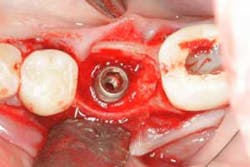

The screw channel of the abutment was accessed by carefully drilling a hole in the center of the occlusal surface using a cross-cut 557 bur (Brasseler) and progressively widening it until the screw channel was accessed (figure 10). Once the screw channel was accessed, the cavit and cotton blocking the screw were removed and the screw was visualized. A driver was placed into the channel to engage the screw and the cement-retained crown was seated on the implant and “screwed” back in place. Complete seating of the restoration was verified radiographically (figure 11). The screw was torqued to 25 Ncm and the access channel was filled with Teflon tape and closed with composite (figure 12). The patient was able to leave with the crown securely in place.

Figure 10:Screw channel accessed.